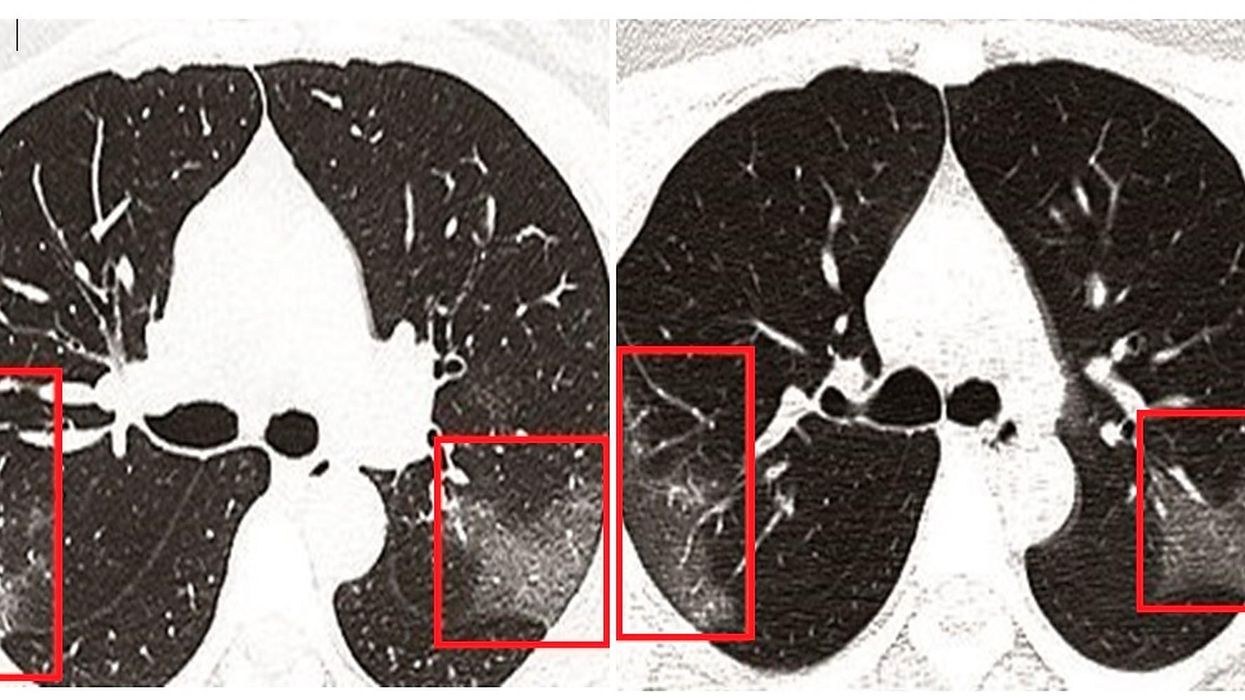

These shocking X-ray scans of 33 year-old coronavirus sufferer shows the effect that the virus can have on human lungs.

After arriving in hospital in China, the woman was quickly diagnosed with Covid-19. Her X-ray scans show white patches in the lower corners of the lungs which indicates what radiologists call “ground glass opacity” – the partial filling of air spaces in the lungs. The white patches appear more pronounced in the second X-ray, on the right, which was taken three days after the first and further into her treatment.

A small proportion of patients develop severe infections which can damage the lungs or cause pneumonia, a condition which causes swelling and fluid build-up in the lungs. Some people who catch coronavirus may not have any symptoms at all, or very mild ones such as a sore throat or a headache.